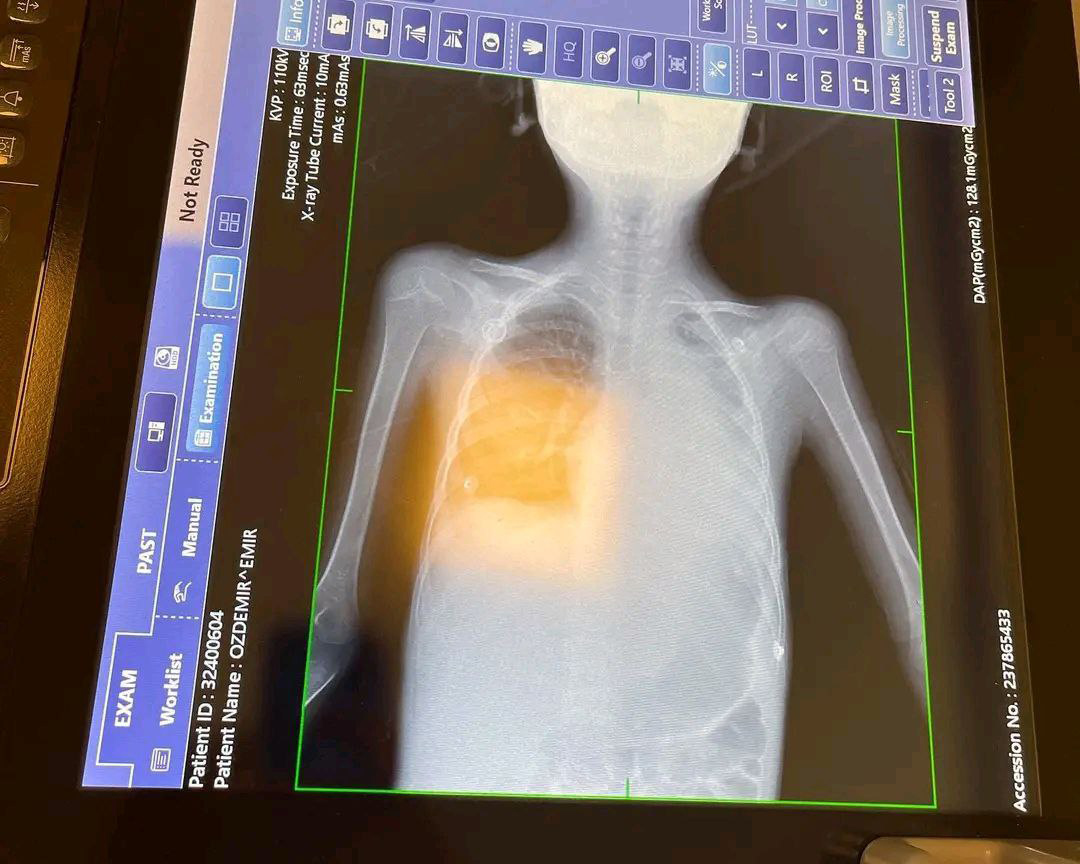

У мальчика диагностировали острый лимфобластный лейкоз — злокачественную онкологию второй стадии, переходящую в третью. Рак повредил все органы, но до клеток мозга не успел добраться.

После полного обследования и анализов у мальчика обнаружили грибковую инфекцию в легких, в результате чего левое легкое перестало функционировать.

Когда антибиотики перестали помогать, врачи решили провести операцию – взять анализ с легких. Мальчика вновь перевели в реанимацию.

Длительные курсы физической терапии избавили Эмира от разных аппаратов и кислородной маски. Врачи планировали удалить одно легкое, чтобы инфекция не распространилась на другие органы.